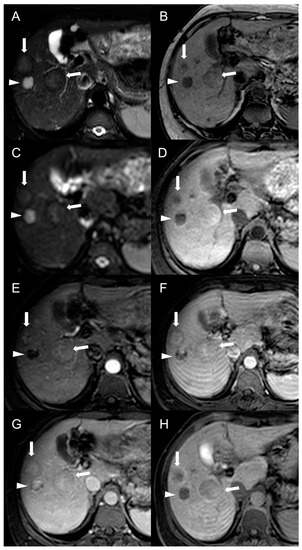

MRI features of FNH-like RNs are shown in Figure 3.

Figure 3.

MRI examination of a 29-year-old female with Budd–Chiari syndrome. On fat-saturated T2-weighted images (A) FNH-like RNs are barely discernable as they appear isointense to the liver parenchyma; occasionally, areas of very slightly hyperintense signal (arrow) can be identified, possibly related to congested nodules or central scar. On out-of-phase T1-weighted images (B) the presence of nodular lesions is more appreciable, as FNH-like RNs (arrow) appear slightly hyperintense compared to the surrounding liver parenchyma. On DWI (b-value = 600) (C), FNH-like RNs may show a slight heterogeneous hyperintensity due to central scar or congestion. On unenhanced gradient-echo T1-weighted images (D), the nodules (arrows) appear hyperintense, while on arterial phase (E) they show vivid enhancement with a peripheral hypointense rim due to hepatic tissue congestion. On portal venous (F) and delayed (G) phases, the nodules become progressively isointense to the liver. On the T1-weighted images (flip angle = 30°) in the hepatobiliary phase (H), FNH-like RNs show hyperintensity compared to the surrounding liver parenchyma.

Besides changes in size, as mentioned above, the MRI features of FNH-like RNs can alter during the follow-up period (Figure 4). For example, the T1 and T2 signal intensity may change, more frequently with a shift from hyperintense to isointense on T1-weighted images and from hypointense to isointense on T2-weighted images. The enhancement pattern may vary as well, with washout acquired in 8% of cases and lost in nearly 20% of cases.

Figure 4.

MRI examinations of a 31-year-old male patient with Budd-Chiari syndrome performed in 2016 (A), 2017 (B), 2018 (C), and 2020 (D). Gradient-echo T1-weighted sequences (flip angle = 30°) acquired in the hepatobiliary phase revealed a 25 mm FNH-like RN (arrows) with central scar and peripheral hyperintensity in 2016 (A). The lesion size grew to 41 mm after 1 year (B) and further to 44 mm after 2 years (C), but it reduced to 35 mm in 2020 (D). Additionally, new FNH-like RNs appeared over time (arrowheads in C,D).